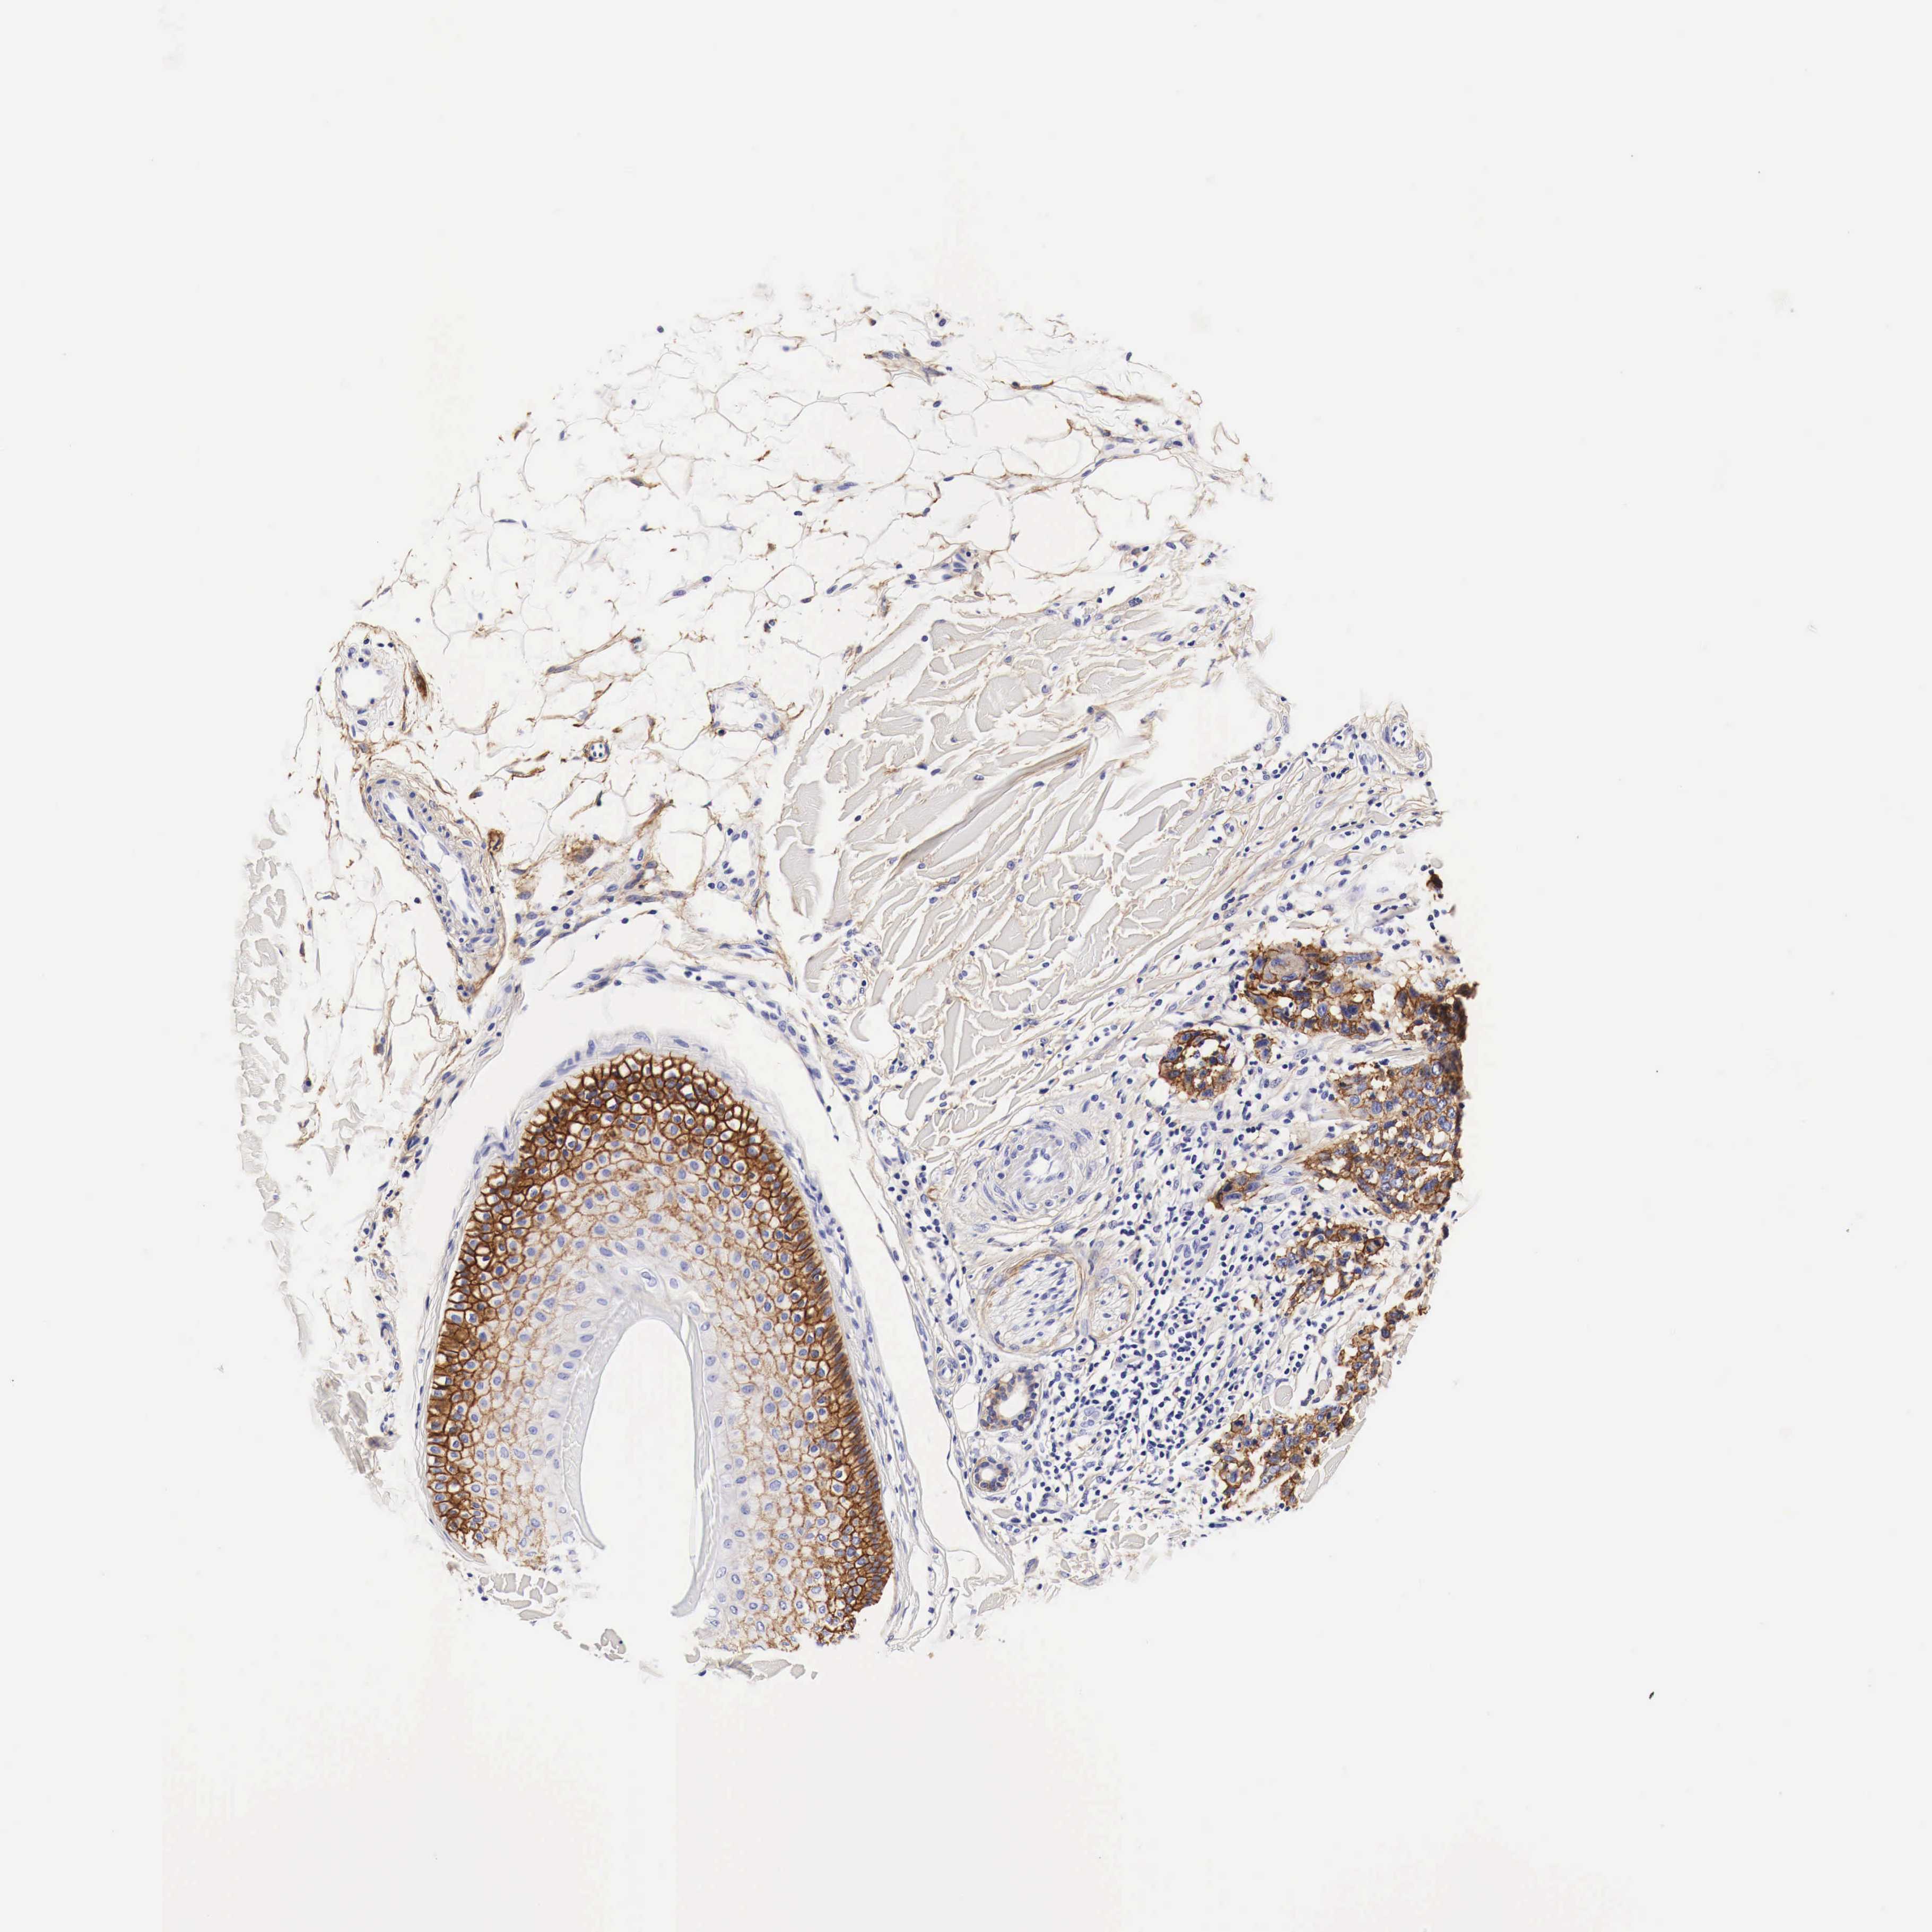

SKIN CANCER - Protein expressioni

A mouse-over function shows sample information and annotation data. Click on an image to view it in a full screen mode. Samples can be filtered based on level of antibody staining by selecting one or several of the following categories: high, medium, low and not detected. The assay and annotation is described here.

Antibody staining in the annotated cell types in the current human tissue is reported as not detected, low, medium, or high, based on conventional immunohistochemistry profiling in selected tissues. This score is based on the combination of the staining intensity and fraction of stained cells.

Each image is clickable and will lead to virtual microscopy that enables deeper exploration of all samples and also displays staining intensity scores, fraction scores and subcellular localization as well as patient and tissue information for each sample.

Squamous cell carcinoma, NOS

Basal cell carcinoma

Squamous cell carcinoma in situ, NOS

Squamous cell carcinoma, metastatic, NOS